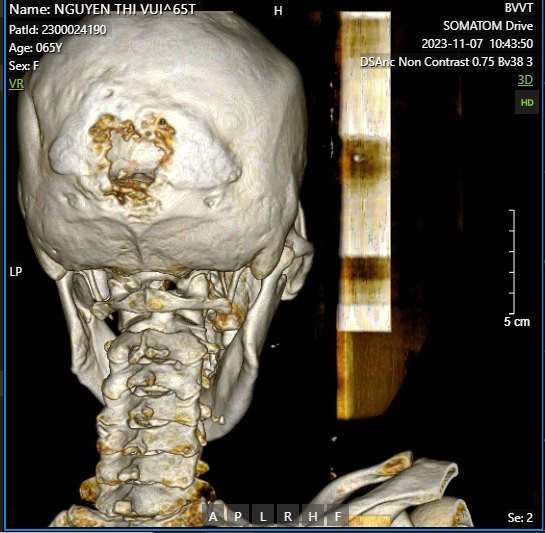

Sau khi được thực hiện các xét nghiệm cơ bản và chụp CT cho thấy ổ dịch hóa ở bao trong trái hướng đến tổn thương cũ, hình ảnh ăn mòn và khuyết xương chẩm vùng đường giữa; kết quả giải phẫu bệnh: Carcinoma vảy sừng hóa xâm nhập.

| Hình ảnh: Chụp cắt lớp vi tính sọ não của người bệnh có hình ảnh ăn mòn và khuyết xương ở xương chẩm |

– Kíp 1 gồm các bác sĩ Phẫu thuật sọ não – cột sống tiến hành cắt bóc u, cắt rộng vùng khối u xâm lấn, dùng khoan máy cắt toàn bộ xương chẩm do khối u xâm lấn vào màng cứng và hội lưu xoang tĩnh mạch dọc trên, lấy bỏ khối u lồi vào trong lòng xoang tĩnh mạch, gửi sinh thiết tức thì để kiểm soát khối u. Tạo hình lại ổ khuyết sọ bằng vật liệu titalum, đảm bảo che phủ hết toàn bộ vùng não bị lộ sau khi cắt bỏ xương sọ của người bệnh, lấy lại sự toàn vẹn của hộp sọ.